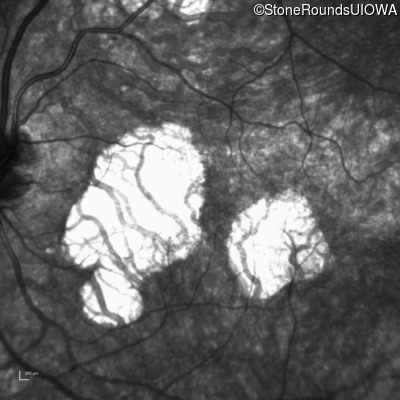

This 31 year old woman had subtle macular abnormalities discovered incidentally earlier that year. Her medical history at the time was unremarkable except for gestational diabetes during her most recent pregnancy. Five years later she was diagnosed with type 2 diabetes managed with oral medication. Two years later she developed sufficient hearing loss that hearing aids were required. Her acuity remained 20/20 OU at that time.

Age at visit: 36 years